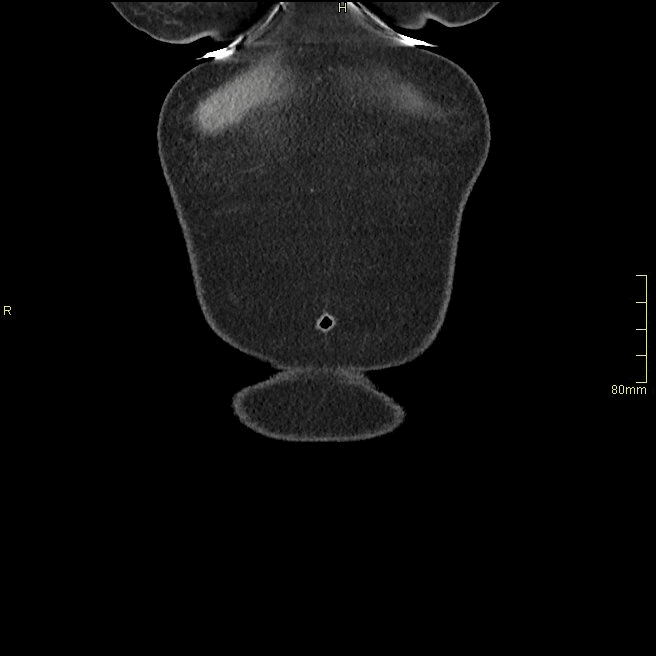

For patients over the age of 40, a non contrast KUB, and seperate nephrogenic and excretory (delayed) phases will be performed. For all patients under the age of 40, a non contrast KUB and a COMBINED dual nephrogenic/excretory phase will be performed. Image examples of this can be seen below.

Under 40 Years of Age

CT Urogram- Nephrogenic + Excretory Phase (Axial)

CT Urogram- Nephrogenic + Excretory Phase (Coronal)

CT Urogram- Nephrogenic + Excretory Phase (Sagittal)